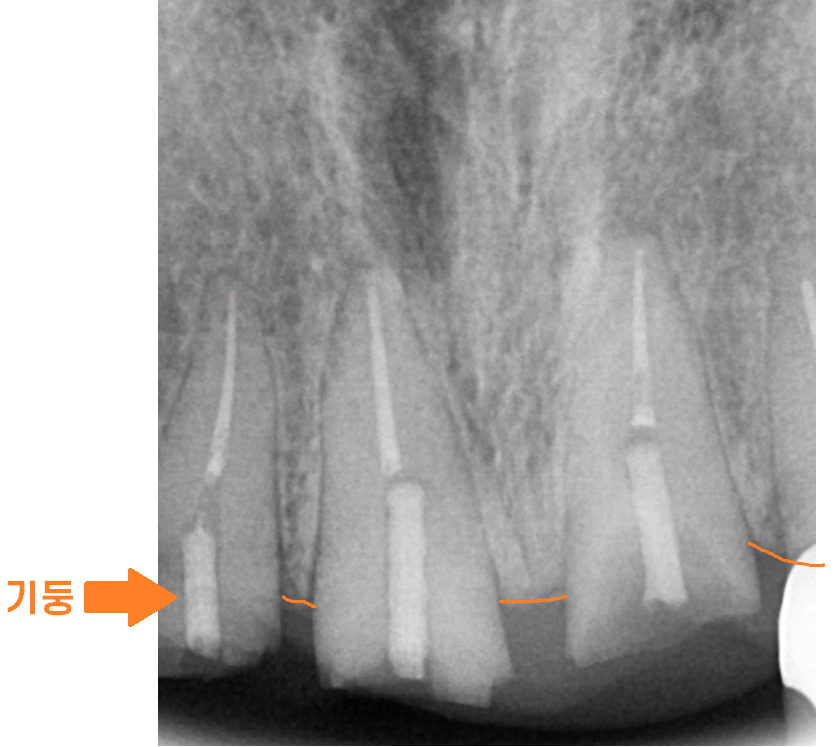

3개의 부러진 앞니

기존에 신경치료 후 기둥까지 보강하여

씌운 치아였는데요.

기존에 치료 이유를 알 수는 없지만

충치가 심했다거나

남아있는 치아의 양이 얼마 되지 않아

기둥까지 심어 치아를 보강하여

치료했던 모양입니다.

상일동역 치과에서 보유한 ct로 남아있는 잇몸 뼈부터 살펴보았습니다.

앞니는 잇몸 뼈가 가장 얇은 부위다 보니

뼈가 없어 임플란트가 어려울 수도 있거든요~

다행히 수술을 하는데 무리는 없어보였습니다.